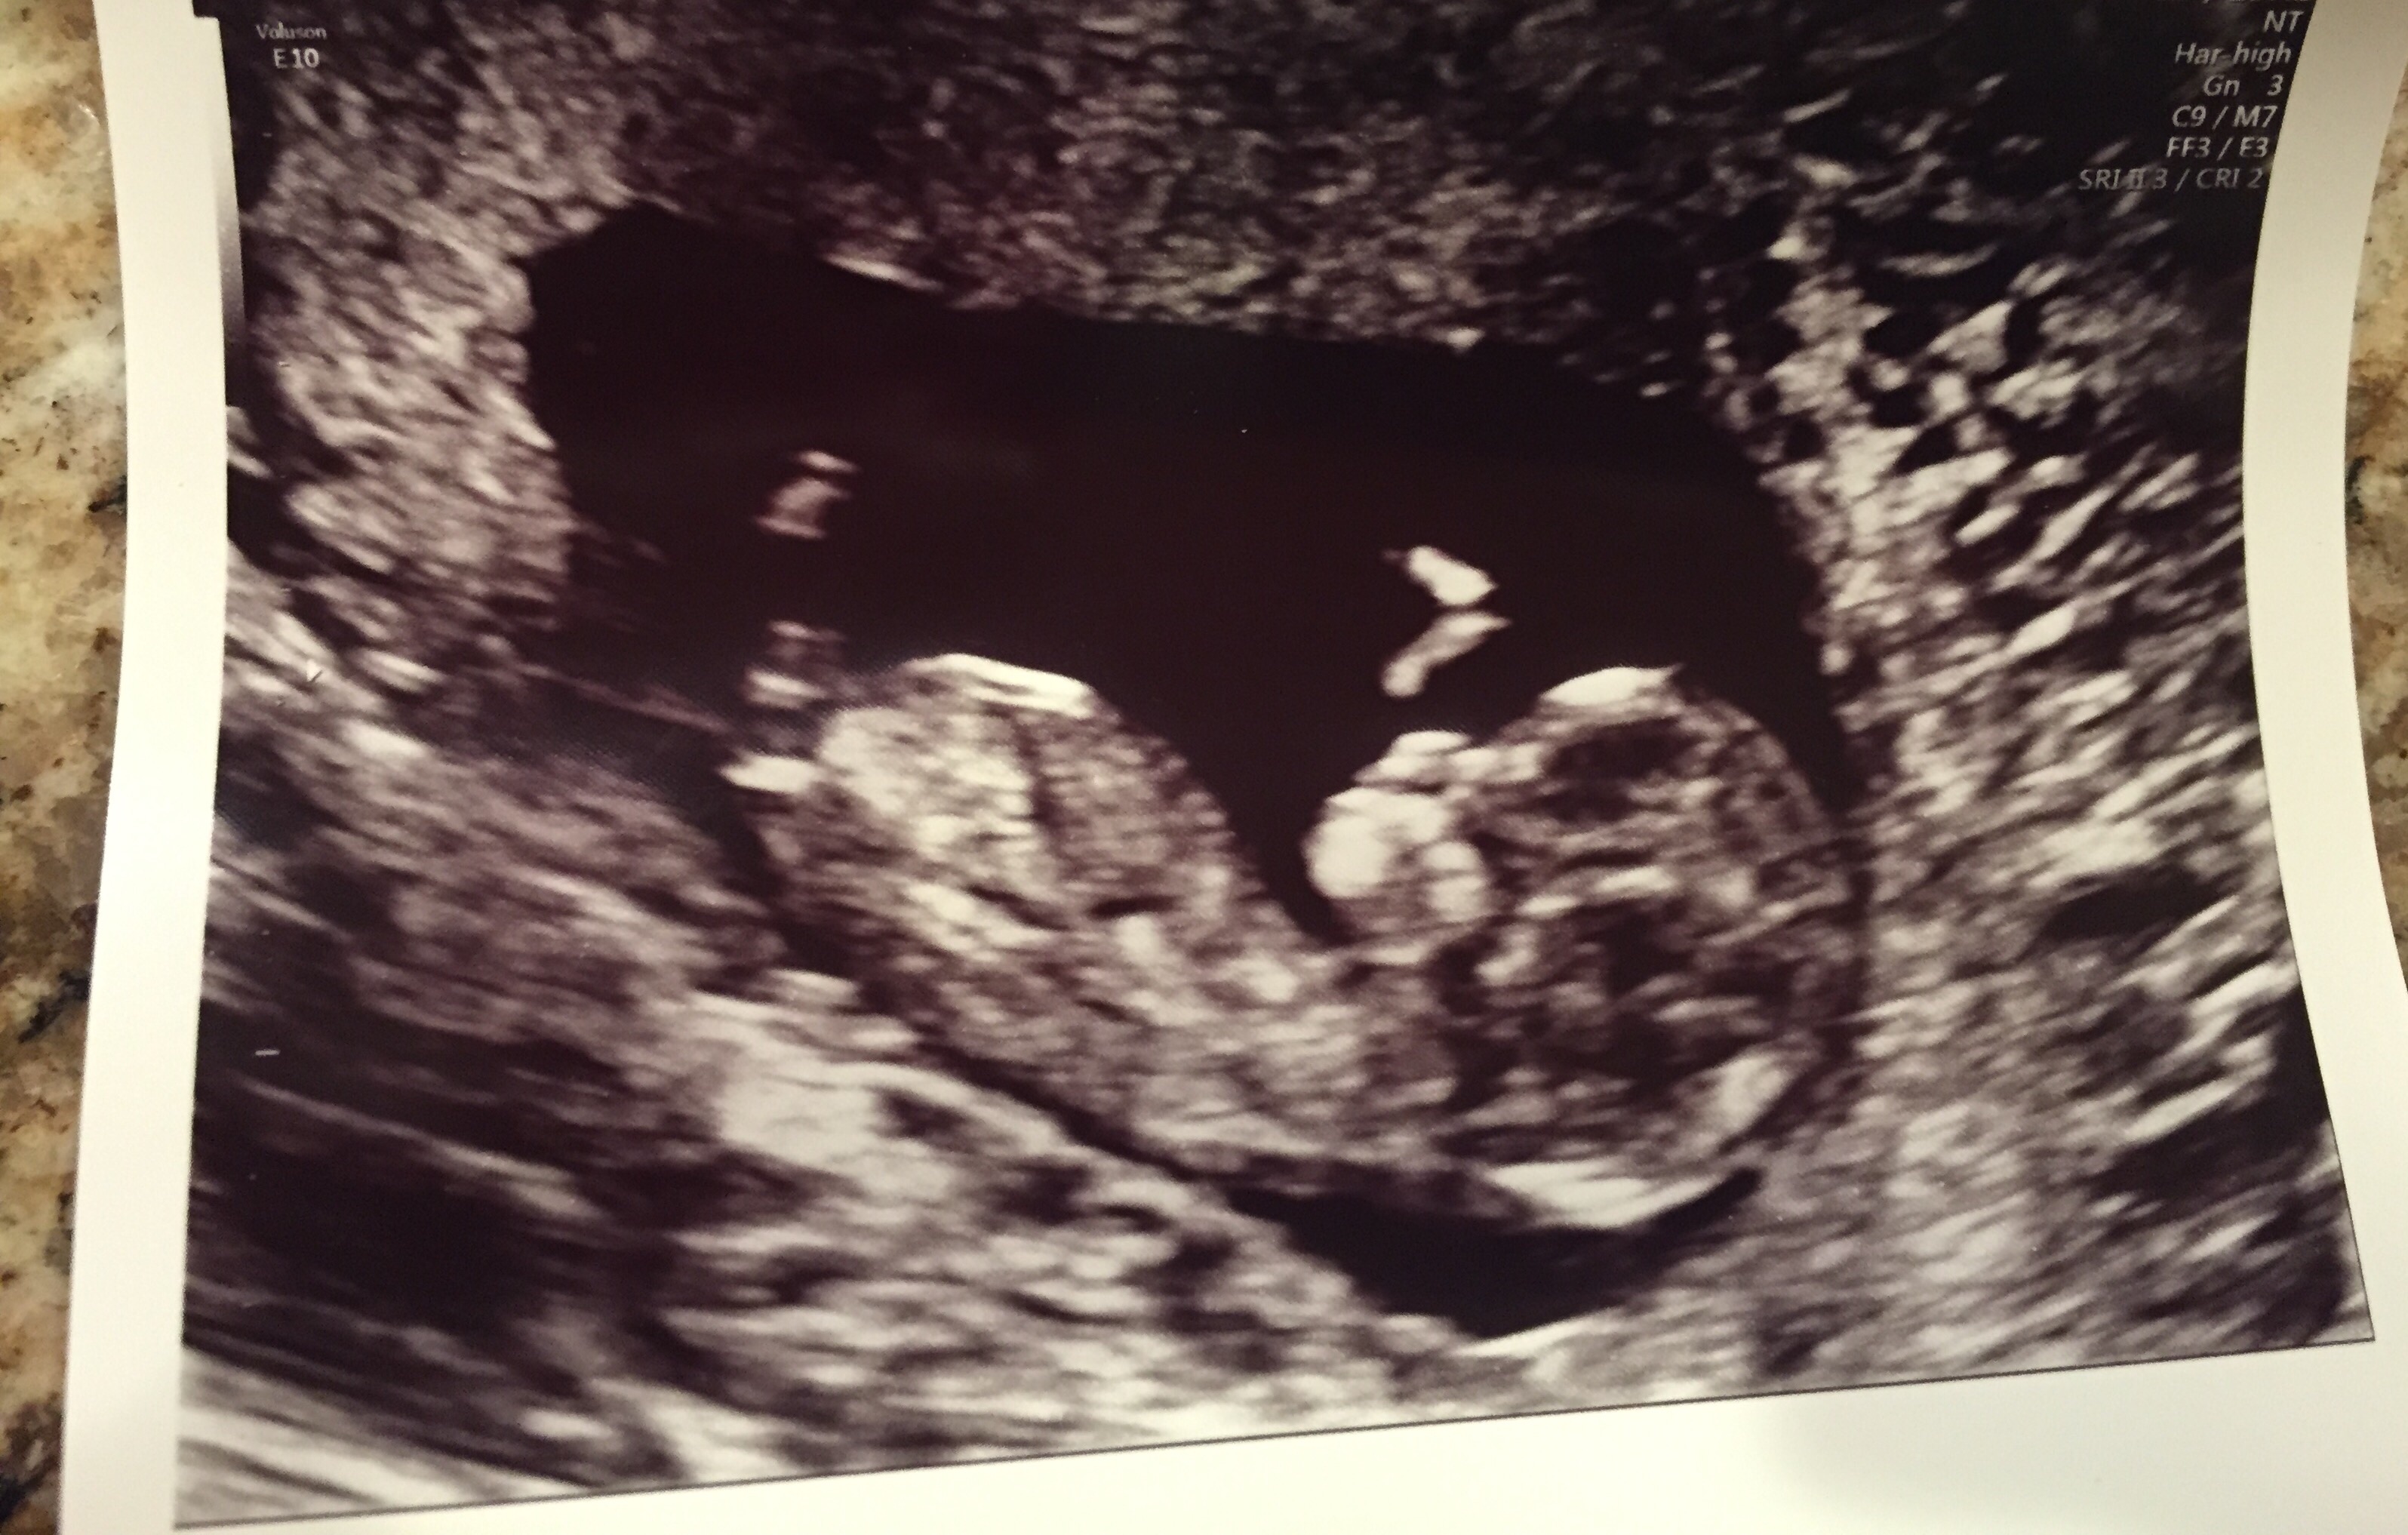

12 weeks 2 days nub theory...any thoughts?? Mama to 3 beautiful boys...Attachment 31385

So is the nub one of the straight white lines or the darker shadows above the white lines?!

If the higher white line is a nub that does look like a girl, but I wonder if that's a leg?